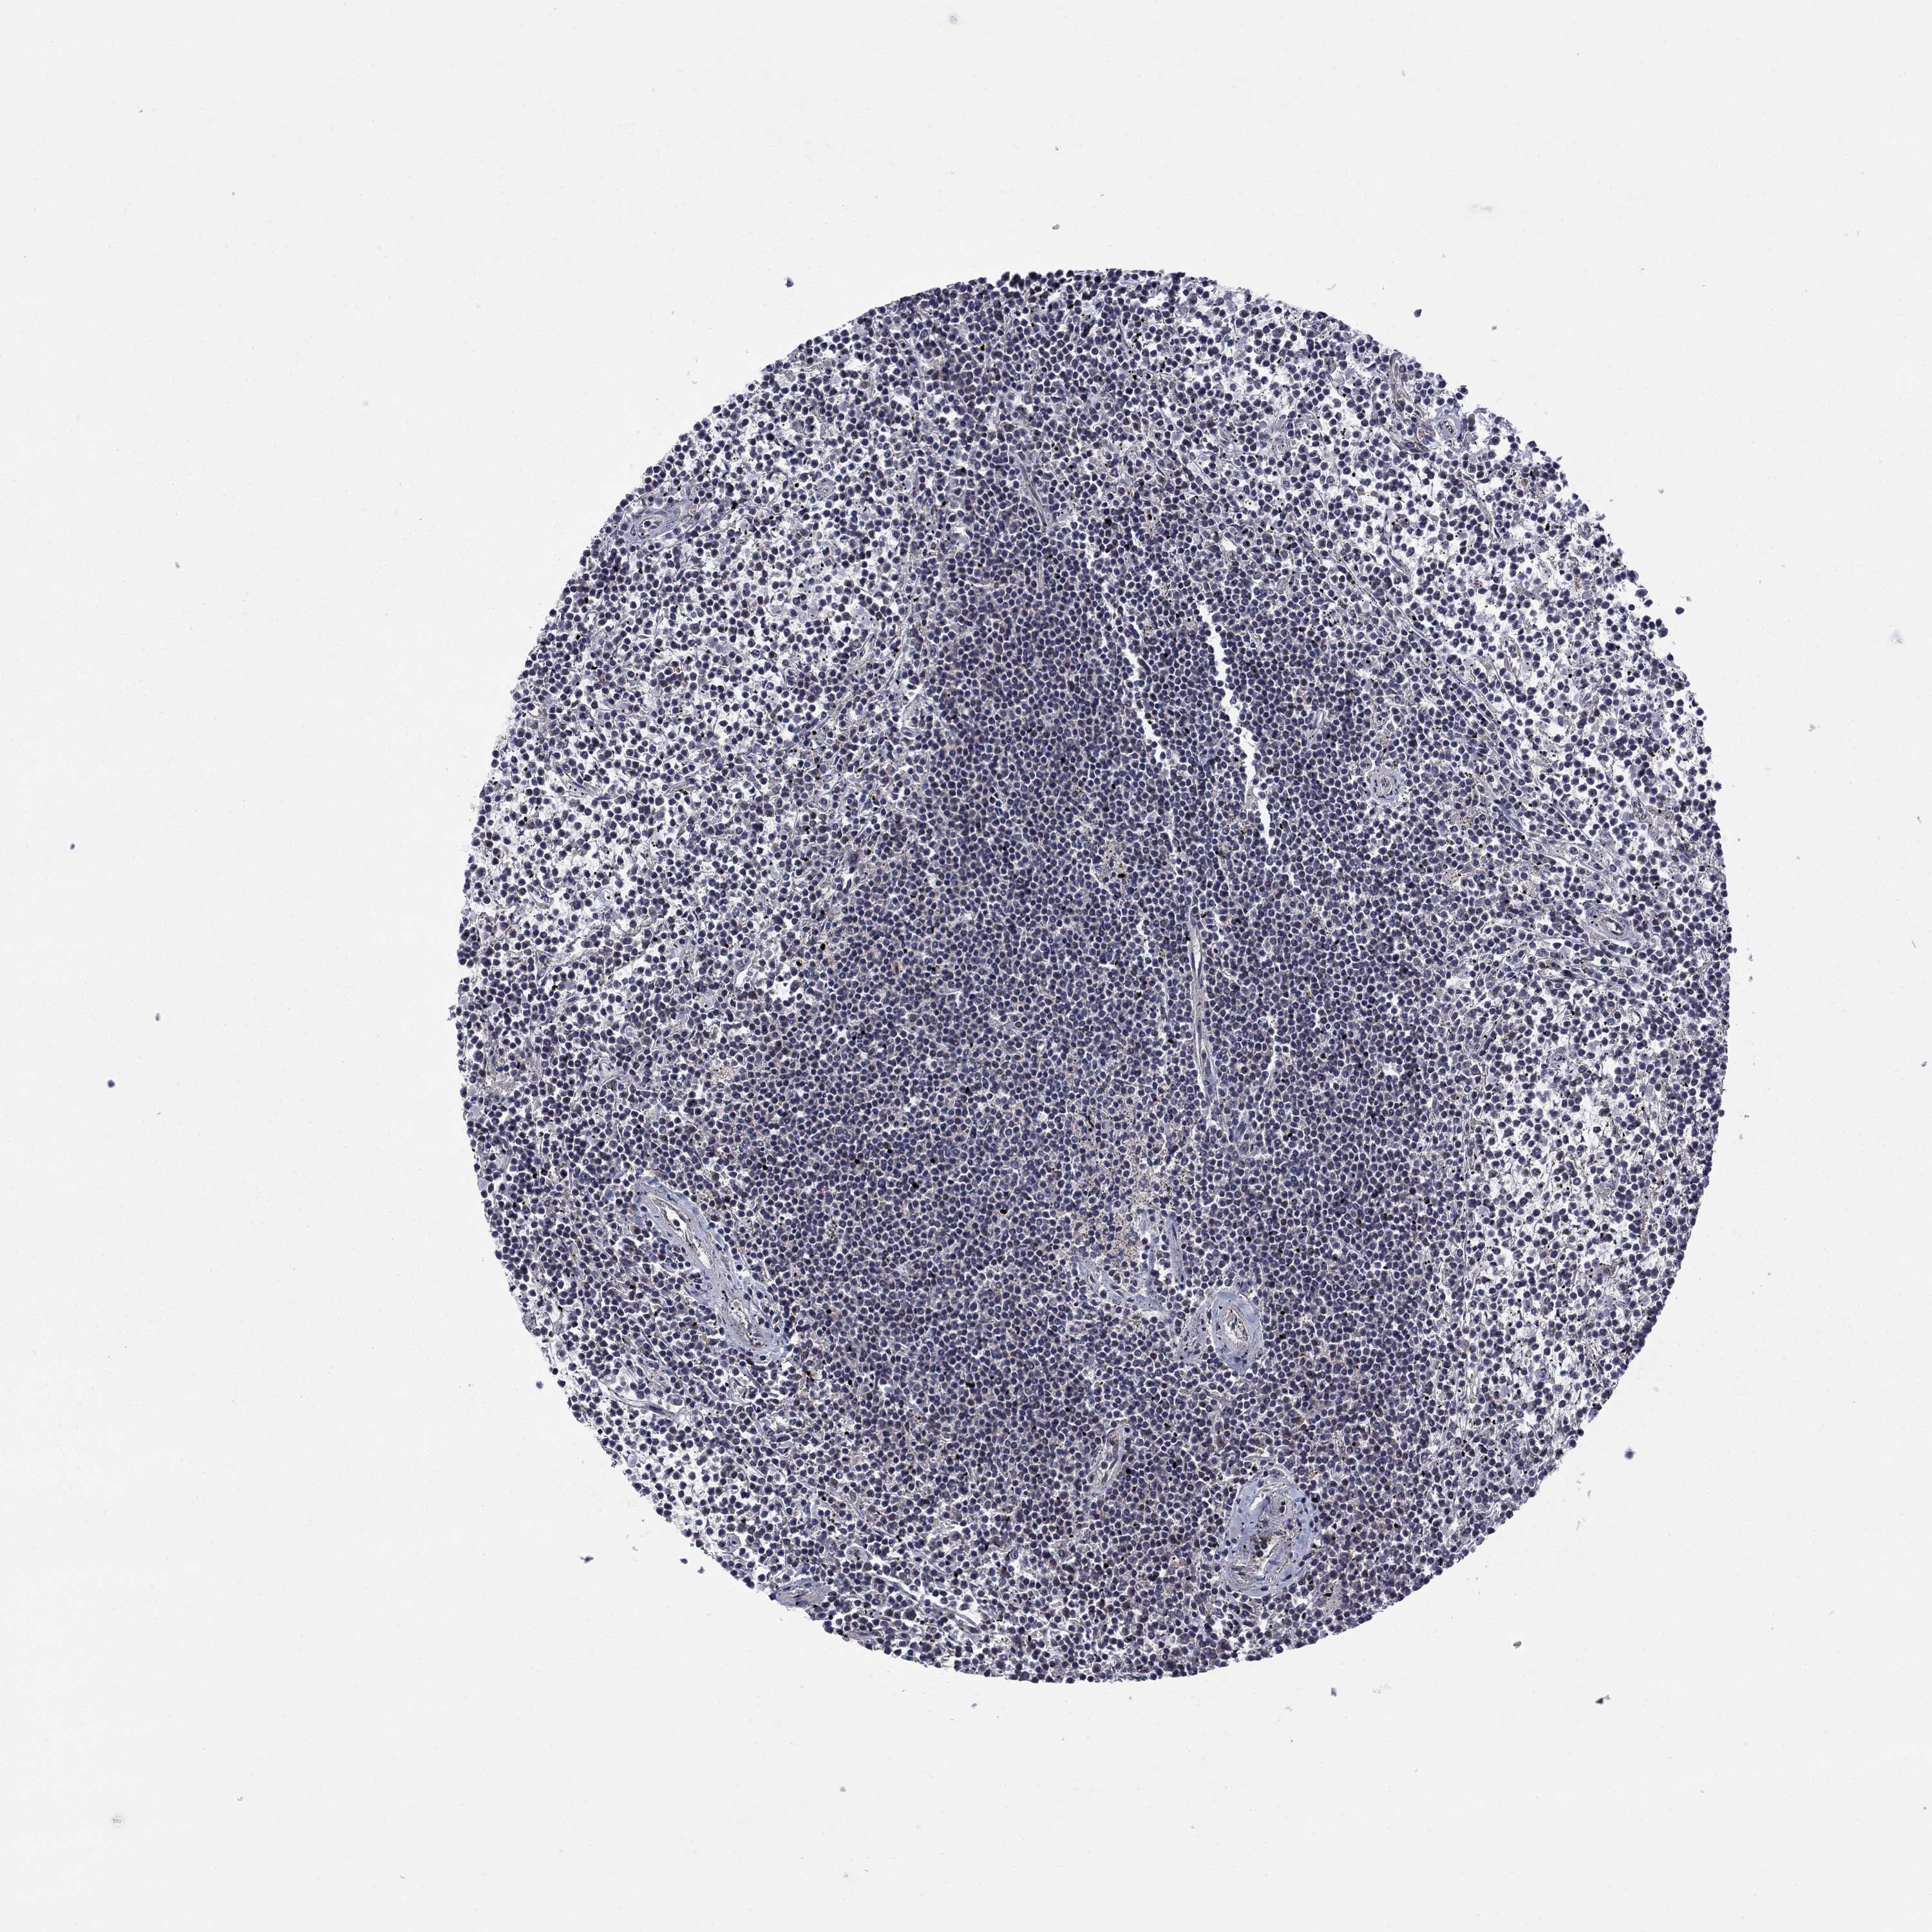

LYMPHOMA - Protein expressioni

A mouse-over function shows sample information and annotation data. Click on an image to view it in a full screen mode. Samples can be filtered based on level of antibody staining by selecting one or several of the following categories: high, medium, low and not detected. The assay and annotation is described here.

Each image is clickable and will lead to virtual microscopy that enables deeper exploration of all samples and also displays staining intensity scores, fraction scores and subcellular localization as well as patient and tissue information for each sample.

Antibody HPA074990

Staining

High

Medium

Low

Not detected

Intensity

Strong

Moderate

Weak

Negative

Quantity

>75%

75%-25%

<25%

None

Location

Nuclear

Cytoplasmic/membranous

Cytoplasmic/membranous,nuclear

Malignant lymphoma, non-Hodgkin's type, Low grade

Malignant lymphoma, non-Hodgkin's type, High grade

Hodgkin's disease, NOS